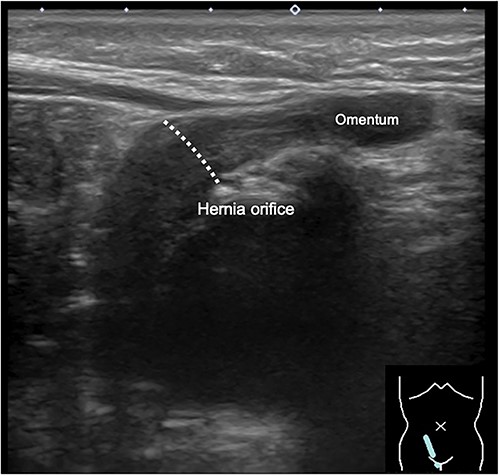

During the newborn’s stay in the NICU, both inguinal regions showed swelling. An ultrasound examination conducted when the infant was 3 months old revealed bilateral inguinal hernias, with the uterus herniating on the right side (Fig. 1). There were no signs of incarcerated hernia, and the urgency of the situation was considered low. As a result, the patient was discharged from the NICU and received outpatient care. At 11 months of age, ultrasound examination was performed, which revealed the presence of omental herniation but no evidence of uterine prolapse (Fig. 2).

Inguinal ultrasound image captured at 11 months of age, showing herniation of the omentum but no apparent protrusion of the uterus.